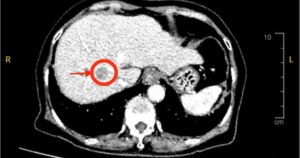

Người đàn ông 50 tuổi đến khám và được phát hiện mắc gan nhiễm mỡ